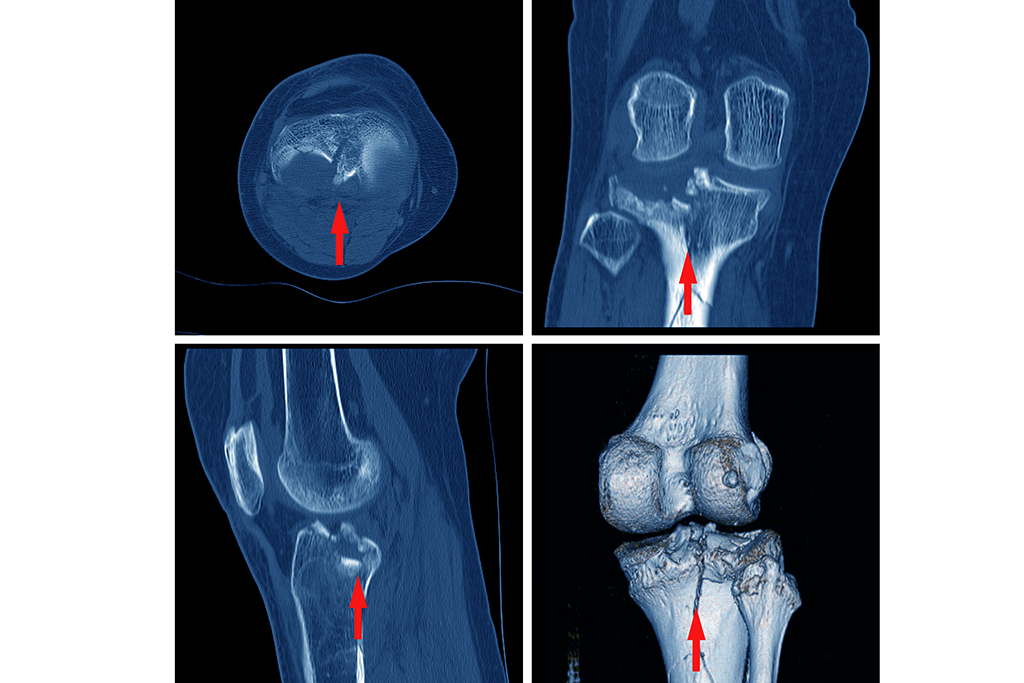

Diagnosticul corect incepe cu o evaluare clinica atenta, urmata de investigatii imagistice. Printre acestea se numara:

radiografii standard (din mai multe unghiuri);

tomografie computerizata (CT);

rezonanta magnetica (RMN) pentru tesuturile moi.

In unele cazuri, se adauga o analiza biomecanica, pentru a evalua functionalitatea piciorului. Aceste informatii ajuta la stabilirea unui plan de tratament adaptat severitatii leziunii.